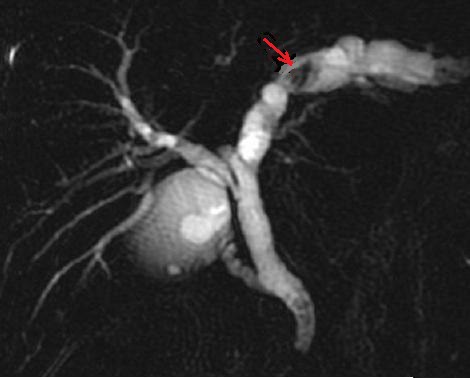

Image radiologique cholangio

- IRM de calcul choledocien et de voie biliaire en

coupe frontal , pondere sur T2 . La bile , le

contenue dans voie biliaire , d'origine de l'eau

sont tres intense ( hypersignal ) et les calcules du

canal choledocque se presence en forme

lacunaire intraluminal sont tres hypointense |

|

-IRM de voie biliaire et de calcul choledocien

recontructive en 3D . Voie biliaire pricipale et des

branches intrahepatiques est tres nette . Le

calcul du canal choledoque est en aspect lacunaire

arrondie a hypointense situe a la portion inferieure

du canal choledoque ( fleche rouge ) . |